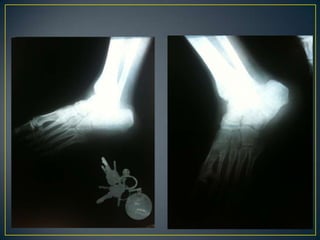

PADECIMIENTO ACTUALInicia el lunes 28 de febrero del 2011 en la tarde, al estar pintando su casa, sufre caída de aproximadamente 8 metros de altura, sin alteraciones de la conciencia, cayendo parado y recibiendo impacto en ambos pies, posteriormente cursa con dolor en ambos calcáneos e incapacidad para deambular, es llevado al servicio de urgencias del IMSS en Altamira donde no puede ser completa su valoración debido a la falta de rayos X, se decide su traslado al IMSS HGR 6 donde es recibido en el servicio de urgencias a las 23:00 horas, se realiza una rx lateral de ambos pies, es diagnosticado por traumatología como fractura multifragmentada de ambos calcáneos, sin lesiones en columna vertebral o cadera, se estable como tratamiento cirugía, se ingresa para su internamiento, sube a piso el 01-03-11 a las 11:45 horas y después se realiza TC la cual confirma el diagnostico antes dado

Diagnóstico: fractura multifragmentada de ambos 	calcáneos 	Tipo III en calcáneo derecho y tipo II según 	Crosby y fitzgibbon y de Sanders

IIIIVVRADIOGRAFÍASSIMPLES 		    TOMOGRAFÍApreoperatoria

II  BTC  preoperatoriaIncongruencia subtalica  post.   :  90 %Conflicto maleolar externo            :  80 %Lesión calcáneo-cuboidea             :  40 %